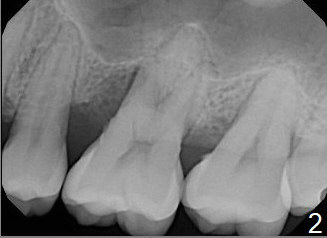

A 41-year-old man has had severe periodontitis at #14 for the last 11 years (Fig.1-3). Finally the tooth is mobile. Draw blood for PRF membrane (x4). After use of Magic Drill with 3 mm stopper, tap Magic Lifter for sinus lift. Insert 1-2 PRF membrane(s) and Vanilla graft prior to further osteotomy with UF drills until 4.5 or 5 mm. Insert tap drill for primary stability. If it fails, switch to IBS dummy implants.